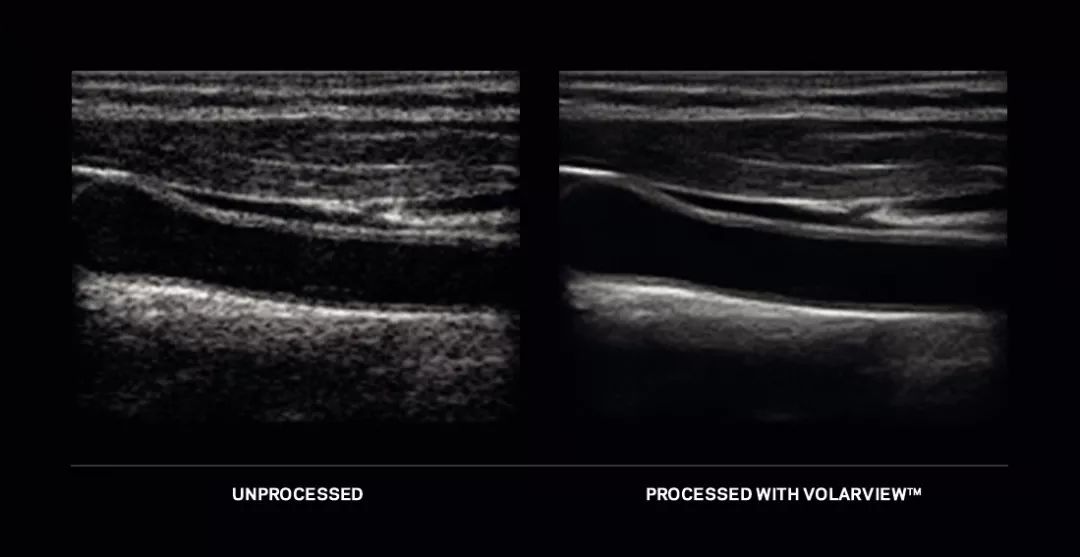

自1983年起,康泰瑞影就为世界医疗影像界提供领先的影像增强软件解决方案,并不断推出全新的软件和专有技术。近日,康泰瑞影在今年的中国国际医疗器械博览会(CMEF)上展出两款全新产品:用于手持超声设备的VolarView™以及用于X光成像的骨科套件。

超声技术没有电磁波辐射,比较安全,设备可应用于各种场合,操作简单。随着手持设备可用性的增加,超声应用已超越传统范围,应用领域和用户变得更为广泛。VolarView™是康泰瑞影推出的可在手机和平板等各类手持设备上使用的解决方案,代表康泰瑞影已经能够为全类别超声系统提供智能影像增强技术,以满足日益增加的照料病患的需求。